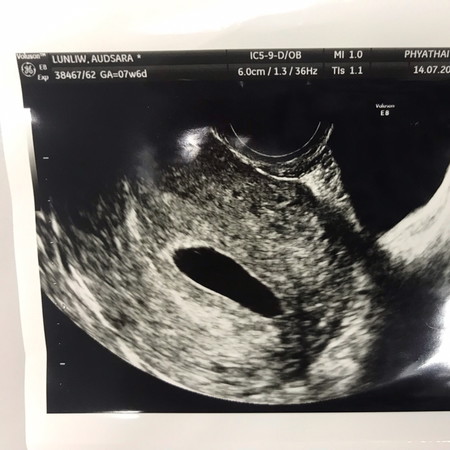

ไปซาวน์ผ่านช่องคลอดมา2ครั้งแล้ว คุณหมอบอกว่า พบแต่ถุงตั้งครรภ์ ไม่พบเด็ก ไม่พบถุงอาหารเลย ไม่มีอาการปวดท้อง ไม่มีเลือดออก ไม่แพ้ท้อง อาการคัดเต้านม ก็ลดลง แบบนี้ท้องลมจริงๆใช่มั๊ยคะ แอบมีหวัง

ลักษณะของถุงตั้งครรภ์เหมือนไม่สมบูรณ์เลยค่ะแม่ ยาวๆ รีๆ น่าจะท้องลมแบบที่คุณหมอว่าค่ะ